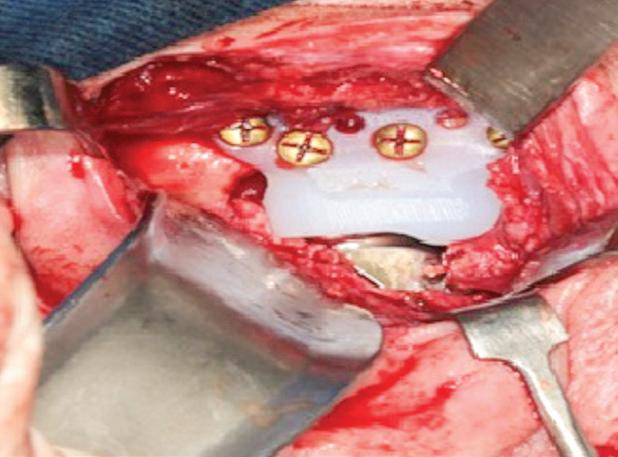

A paciente foi submetida à reconstrução total bilateral com próteses de estoque do sistema Biomet (Biomet 3i do Brasil Ltda., São Paulo/SP, Brasil). Foram realizados, bilateralmente, acessos pré-auricular e retromandibular, condilectomia e, por fim, instalação das próteses de estoque. A sequência da instalação das próteses consistiu em primeiro o componente fossa e, depois, o componente mandibular (Fig. 2). O paciente encontra-se aos cinco anos de pós-operatório, com uma boa abertura de boca e oclusão preservada e sem dor (Fig. 3).

Figura 2: A) Acesso pré-auricular direito. B) Acesso pré-auricular esquerdo. C) Componente mandibular direito instalado na face lateral do ramo da mandíbula através do acesso retromandibular. D) Componente fossa direito instalado na base do crânio através do acesso pré-auricular. E) Componente mandibular esquerdo instalado na face lateral do ramo da mandíbula através do acesso retromandibular. F) Componente fossa esquerdo instalado na base do crânio através do acesso pré-auricular.